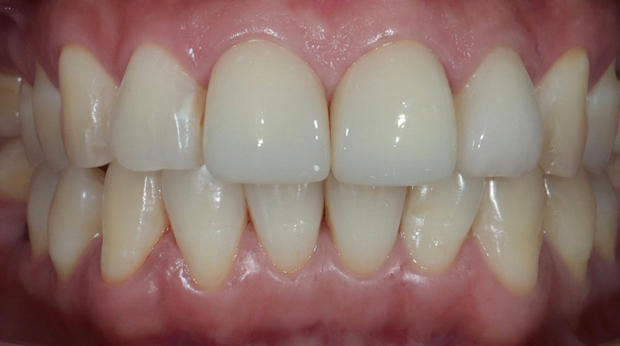

라미네이트